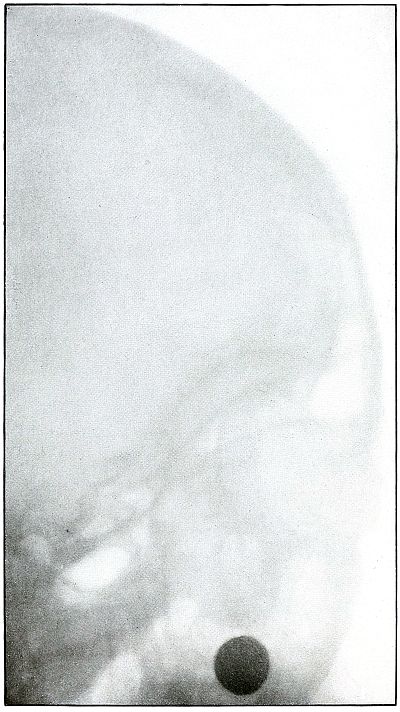

Rifle—Plate 1.

HEAD.

Gunshot Fracture of the Skull,

with Lodgment of the Missile.

The bullet in this case was so badly deformed by ricochet that

part of both core and jacket were lost. While the appearance of the

shadow seems to indicate a direct impact of the nose of the bullet,

the line of contact with the skull must have been tangential, with

some laceration of the scalp; otherwise a cursory examination of the

scalp wound would have revealed the slightly protruding end of the

bullet. The dark shadow above the projectile is due to material used

in dressing. The great thickening of the scalp in the region of the

wound shows a marked cellulitis. Small particles of the lead core of

the bullet can be seen about the wound.

In such cases there is often a marked infection of the scalp

without extension of infection to the cranial cavity, except from

neglect. This is a case, though apparently simple, in which the

radiograph was necessary for correct diagnosis without exploration.

The treatment in such cases is conservative, with removal of

the projectile and care of the superficial infection or subsequent complications.